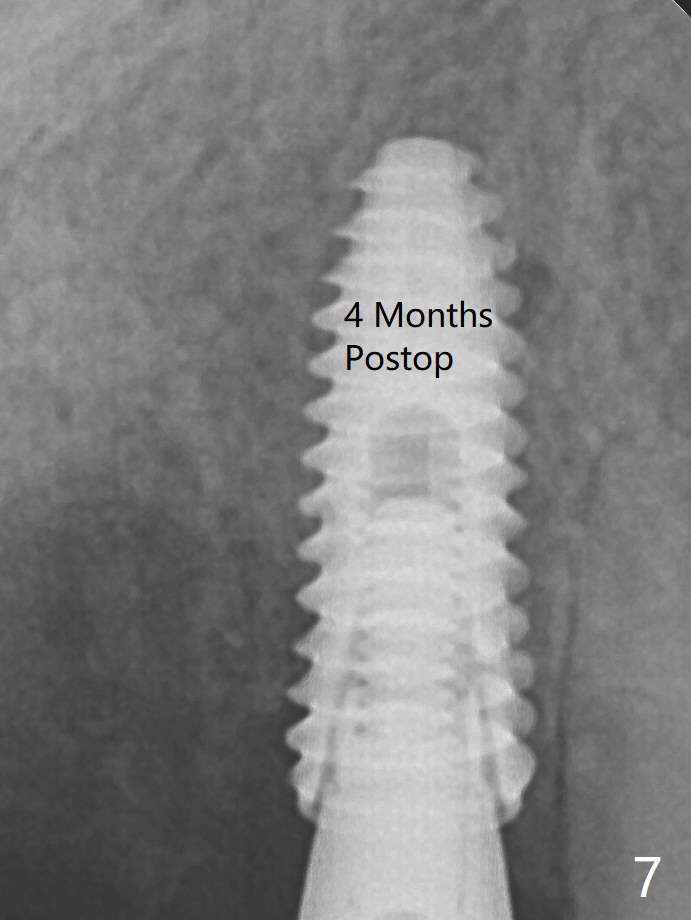

Once an abutment is placed at #5 (Fig.2 A, 5) for temporary crown (Fig.4 T) , the guide may be not seated again unless the crown is removed. Allograft (*) not only covers the exposed implant threads, but also the denuded root surface of the canine.  The implant seems to be covered by the bone 4 months postop (Fig.7).  In fact the abutment has not been seated completely.